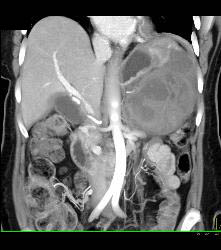

GIST Tumor